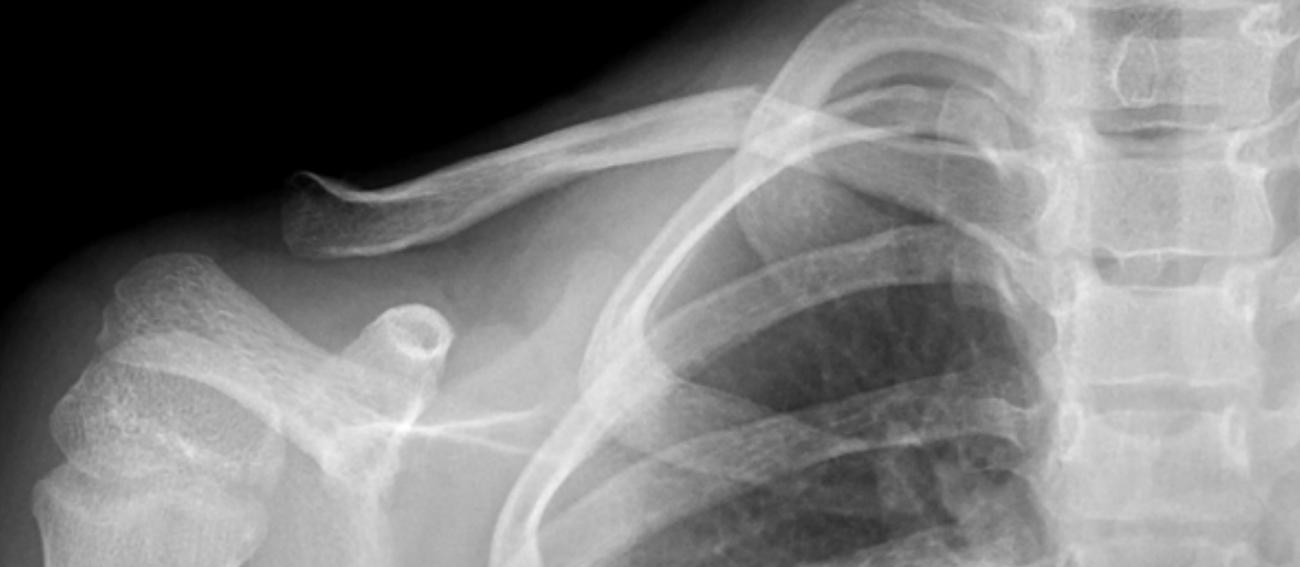

不全骨折(青枝骨折)

锁骨骨折吃什么食物最好,锁骨骨折怎么绑绷带视频

完全骨折